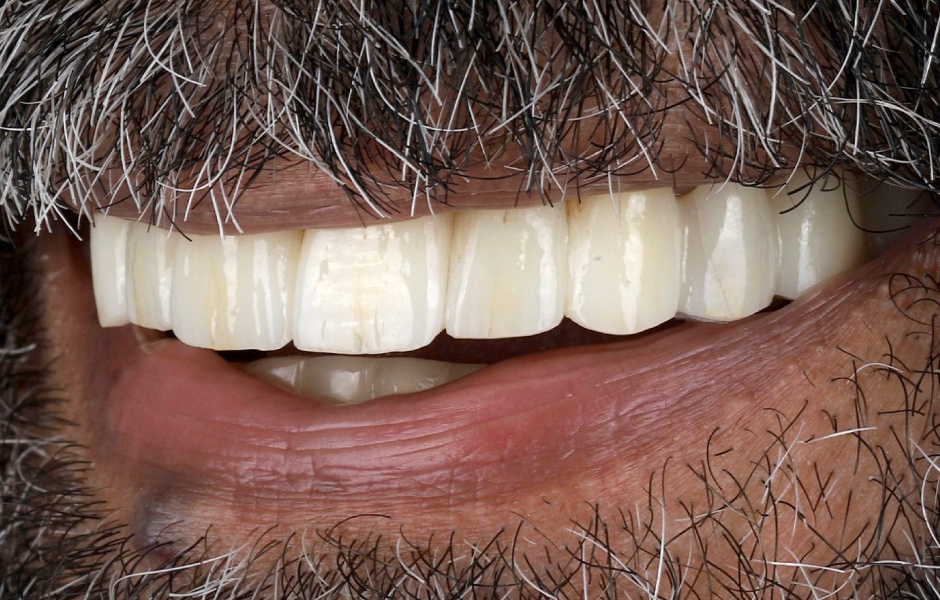

Definitivní náhrada byla nasazena a ověřena z hlediska estetiky, okluze a funkce (obr. 51–55). Panoramatický kontrolní snímek potvrdil, že všechny parametry protetického ošetření odpovídají očekávaným hodnotám (obr. 56).

Při kontrole po 18 měsících po dokončení ošetření bylo provedeno intraorální, extraorální a radiografické vyšetření. Nebyly zjištěny žádné patologické nálezy a výsledné parametry zůstaly stabilní (obr. 57–62).

Obr. 51

Obr. 52

Obr. 53

Obr. 54

Obr. 55